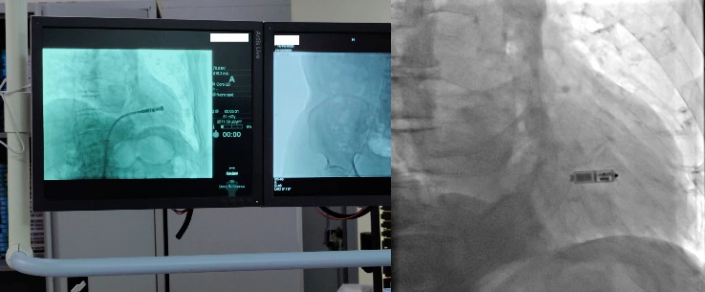

2022年11月16日,心血管内科三病区心脏介入团队在科主任孙林教授指导下,成功完成一台新一代双腔无导线起搏器植入术,通过右侧股静脉在患者心脏内“扎根”,让患者重获“心”生。

无导线起搏器是一种新兴的心脏起搏器,让“不开刀即可安装起搏器”的梦想成为现实。它身形小巧,只有胶囊大小,重仅2克。但却拥有超强的电池续航能力,寿命超过12年。同时兼容1.5T/3.0T核磁共振扫描,可满足患者之后疾病诊断需求。与传统心脏起搏器相比,双腔无导线起搏器体积减少93%,整个手术过程时间短,植入成功率高。可以保存心房、心室的顺序收缩功能,实现生理性起搏功能,开启了“无导线起搏新时代”。该技术的成功开展,是财神捕鱼玩法攻略与赚钱技巧指南 | 财神捕鱼游戏网 心血管内科三病区不断开展新技术、持续提升服务水平的生动注脚。未来,心血管内科将持续推进该项技术的普及,为更多患者的“心健康”保驾护航。